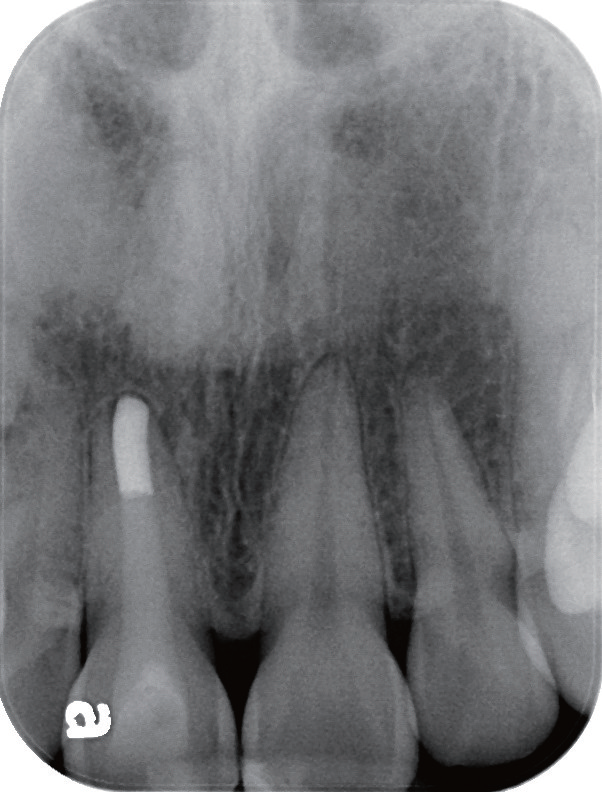

预后   根管治疗后半年(图16)、两年半(图17~18)、三年半(图19)患者前来复诊,可见11根尖恢复良好,已完全愈合,随后进行全冠修复,完成患牙的全部治疗。

图16 根充半年后,患者自觉按压11 根部牙龈时,虽无不适但改善并不明显;X线片显示11 根尖放射性阴影边界变模糊,这是病灶开始愈合的表现

图17 根充两年半后,患者自觉11 牙冠颜色较暗,复诊咨询是否可以进行美白治疗;鉴于治疗前11 唇侧已有数条裂纹,建议用全瓷冠修复较为合适

图18 根充两年半后,患者自觉按压和敲击11时无明显不适,X 线片显示原根尖骨组织缺损逐步愈合,可见根尖牙槽骨板重现

图19 根充三年半后,X 线片可见11 根尖牙槽骨板完整,覆盖突出的牙胶尖,原开口的根尖于治疗后已经闭合